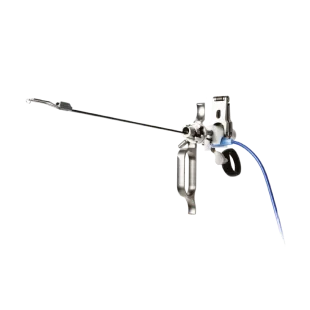

-

Rezum 리줌 수증기 치료 시스템

Rezum 리줌 수증기 치료 시스템 -

프로게이터 (2세대 전립선 결찰술)